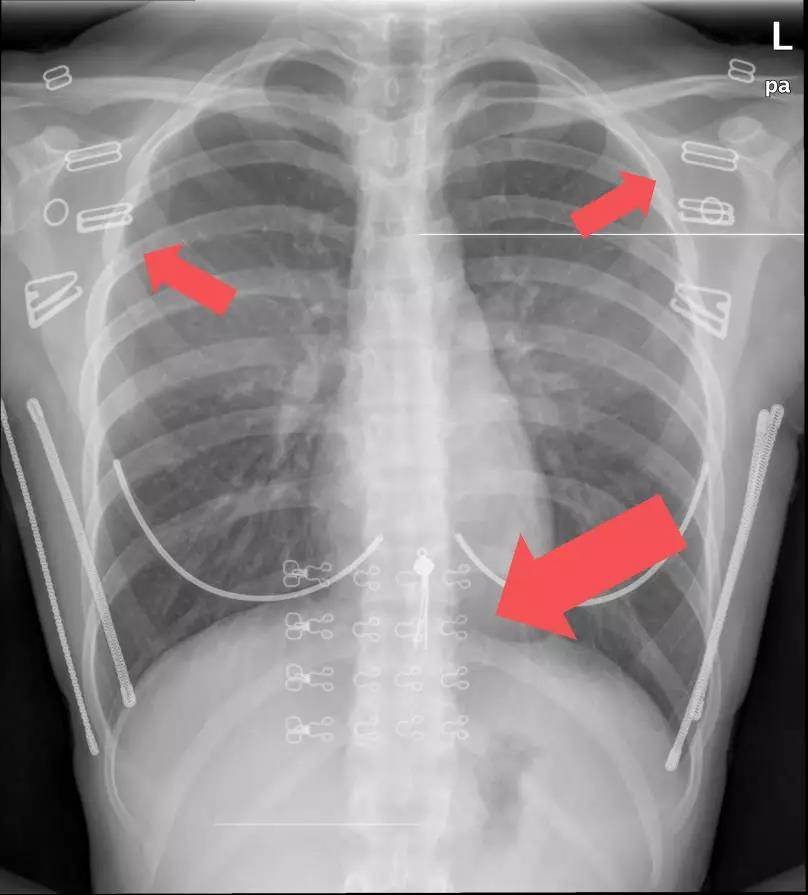

下图是没有去除文胸,衣服装饰品的:

文胸上的扣子和钢圈,衣物上的装饰物较多,有亮珠片、金属纽扣、印刷图案、反光带......拍片前应该先去除这些干扰因素。因为这些体外的异物遮挡了我们所要观察的肺野和肋骨,如果刚好这些位置有病灶,就会被体外的异物遮挡住了,影响图像质量,从而导致误诊、漏诊。